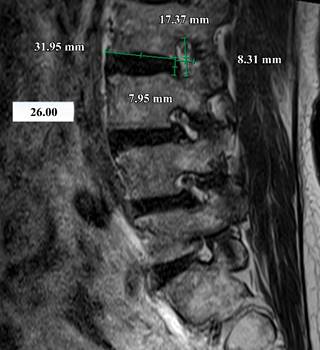

All measurements were conducted by a resident physician in traumatology and orthopedics, who assessed the foramina from L1-S1, and performed the following measurements: 1) Foraminal height, measuring the distance between the pedicles; 2) Foraminal width, extending from the posterior edge of the vertebral body to the anterior edge of the superior articular process. In cases where there were two posterior edges due to obliquity or rotation of the vertebral body, the most posterior edge of the vertebral body was taken as a reference. 3) Lower endplate, measured from its anterior limit to its posterior edge; 4) Posterior disc height, measured as the distance between the posterior edges of the vertebral endplates. These measurements are illustrated in Figures 1 and 2.

Figure 2: Lumbar plain magnetic resonance imaging in T2 sequence with sagittal view. Combined measurement of foraminal height and width, inferior endplate, index of foraminal width/inferior endplate with a result of 26%, and measurement of posterior disc height.

Following the measurements, the foraminal width/lower endplate (FW/LE) index was calculated. This index is obtained by dividing the measured foraminal width by the lower endplate measurement and multiplying the result by 100 to express it as a percentage.

During this study, a consensus was reached among 3 spine surgeons in the service, establishing that a foraminal width/lower endplate index of less than 10% suggests performing direct decompression. This decision is based on the inference that with a bone distance of less than 4 mm in foraminal width, there will be compression and morphological changes of the nerve, despite the removal of soft structures such as intervertebral disc or ligamentum flavum. This inference is supported by the understanding that the nerve root occupies approximately between 23.89 and 32.18% of the foraminal area depending on the lumbar level.11,13